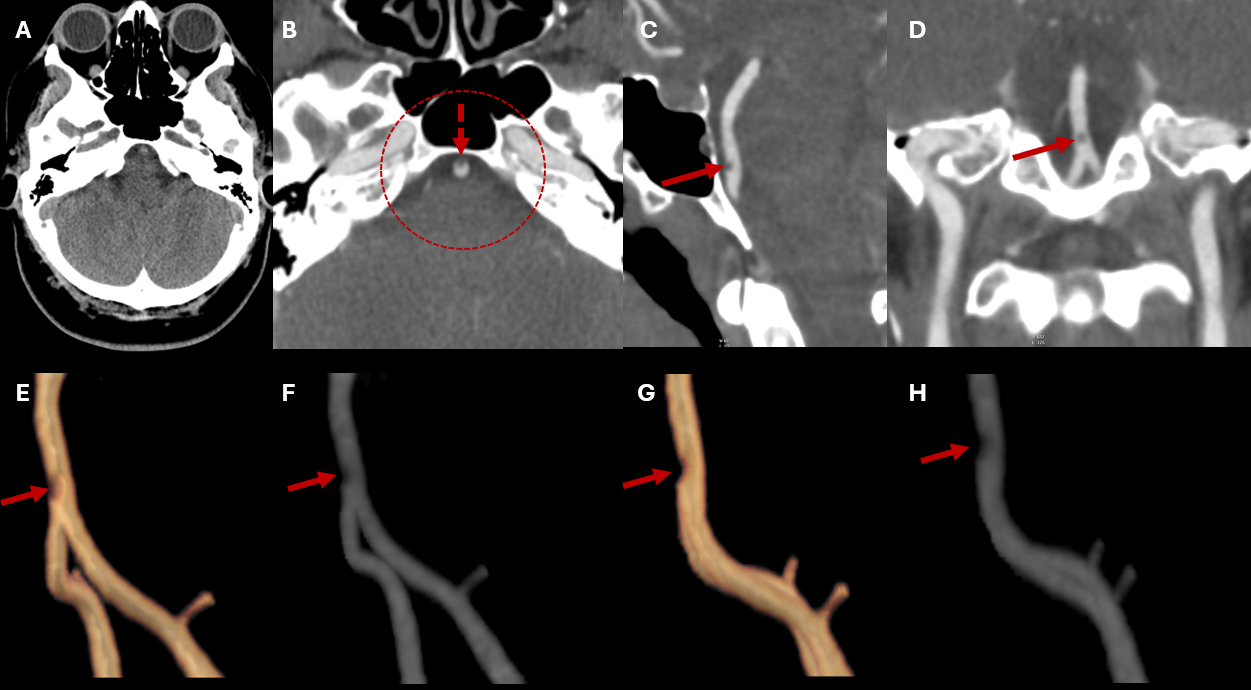

Figure 1: Non-contrast head CT (A) and CT angiography (B-H) of the posterior circulation. The non-contrast CT shows no hyperdense abnormalities. On CTA (B), a small focal intraluminal filling defect is seen along the anterior wall of the proximal basilar artery (arrow). Zoomed-in views in sagittal, coronal, and oblique reconstructions (C-H) better demonstrate this focal luminal defect, whose appearance is consistent with a thin membranous web.

A 40-year-old woman presented with a sudden onset of severe headache. She denied focal neurological deficits or previous similar episodes. Her medical history was unremarkable, but she reported a family history of cerebral aneurysm. Non-contrast head CT showed no evidence of hemorrhage or infarction (not shown). Intracranial CT angiography (Fig. 1) revealed a small focal filling defect along the anterior wall of the proximal third of the basilar artery, characterized by a thin membrane protruding into the vascular lumen, consistent with a basilar artery web. No aneurysm, dissection, or significant stenosis was identified. The patient was managed conservatively with antiplatelet therapy and remains under clinical and imaging follow-up.